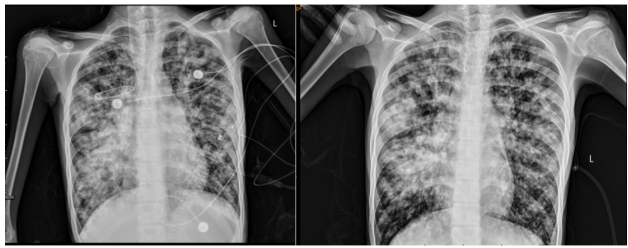

8月28日复查胸部X线片两肺弥漫渗出、局部实变,右肺为著(图8)

图8  床旁胸部X线片(左为8月28日,右为8月11日)

现患者症状好转,感染指标下降(图9),胸部X线片较前好转,囊性纤维化诊断明确,家属要求转院评估肺移植。